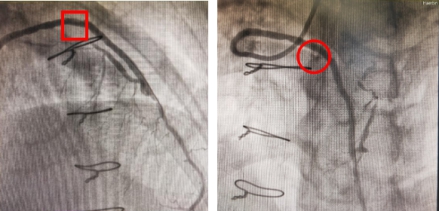

右冠静脉桥血管药物球囊治疗前后影像对比